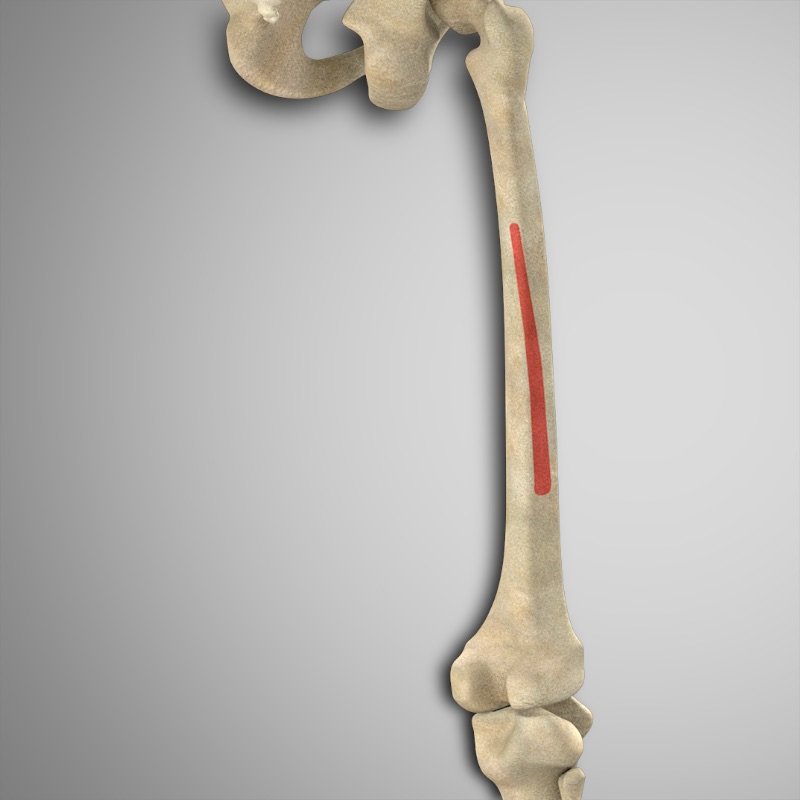

- Bíceps femoral (cabeza larga) – Tuberosidad isquiática

- Bíceps femoral (cabeza corta) – Linea Aspera